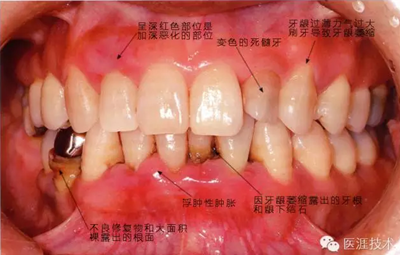

正在服用高血壓藥中的56歲男性。菌斑控制得不好。通過牙周探診,全頜有4~6mm的牙周袋,在X光片中可以看到全頜中度牙槽骨吸收,磨牙處一個地方是重度牙槽骨吸收。通過比較牙周病進展狀態(tài),邊緣部有大范圍浮腫(發(fā)紅、腫脹),和纖維性肥厚。這也可能是服用中的降壓藥的副作用導(dǎo)致的。因為牙齦、牙槽骨比較厚,牙齦呈架子狀。